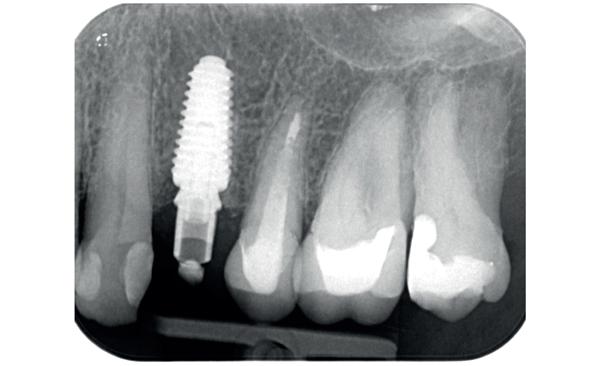

De implantaatplaatsing en de beslissende fout (afbeelding 1-13)

De extractie verliep voorspoedig, waarbij ik zoals al-

primaire stabiliteit van 60 Ncm.

11. Röntgenfoto ter controle van de plaatsing en de angulaire. Dit bone-level implantaat werd 4 mm onder de weke delen geplaatst.

12. Direct post-op. Een direct geplaatste tijdelijke kroon. Vastgezet met een torque van 20 Ncm en gehecht met prolene 5/0.

tijd probeerde de buccale botlamel intact te houden. Dit is cruciaal voor latere botbehoud en implantaatplaatsing. Na curettage en spoelen van de alveole beoordeelde ik de situatie opnieuw: de botcondities leken gunstig voor een immediaat implantaat.

Hier begon echter de cruciale fout in mijn klinisch besluitvormingsproces. In mijn streven naar maximale primaire stabiliteit - wetende dat immediaat belasten enkel mogelijk is bij hoge stabiliteit -on-

13. Röntgenfoto ter controle van de pasvorm van de direct geplaatste tijdelijke kroon.